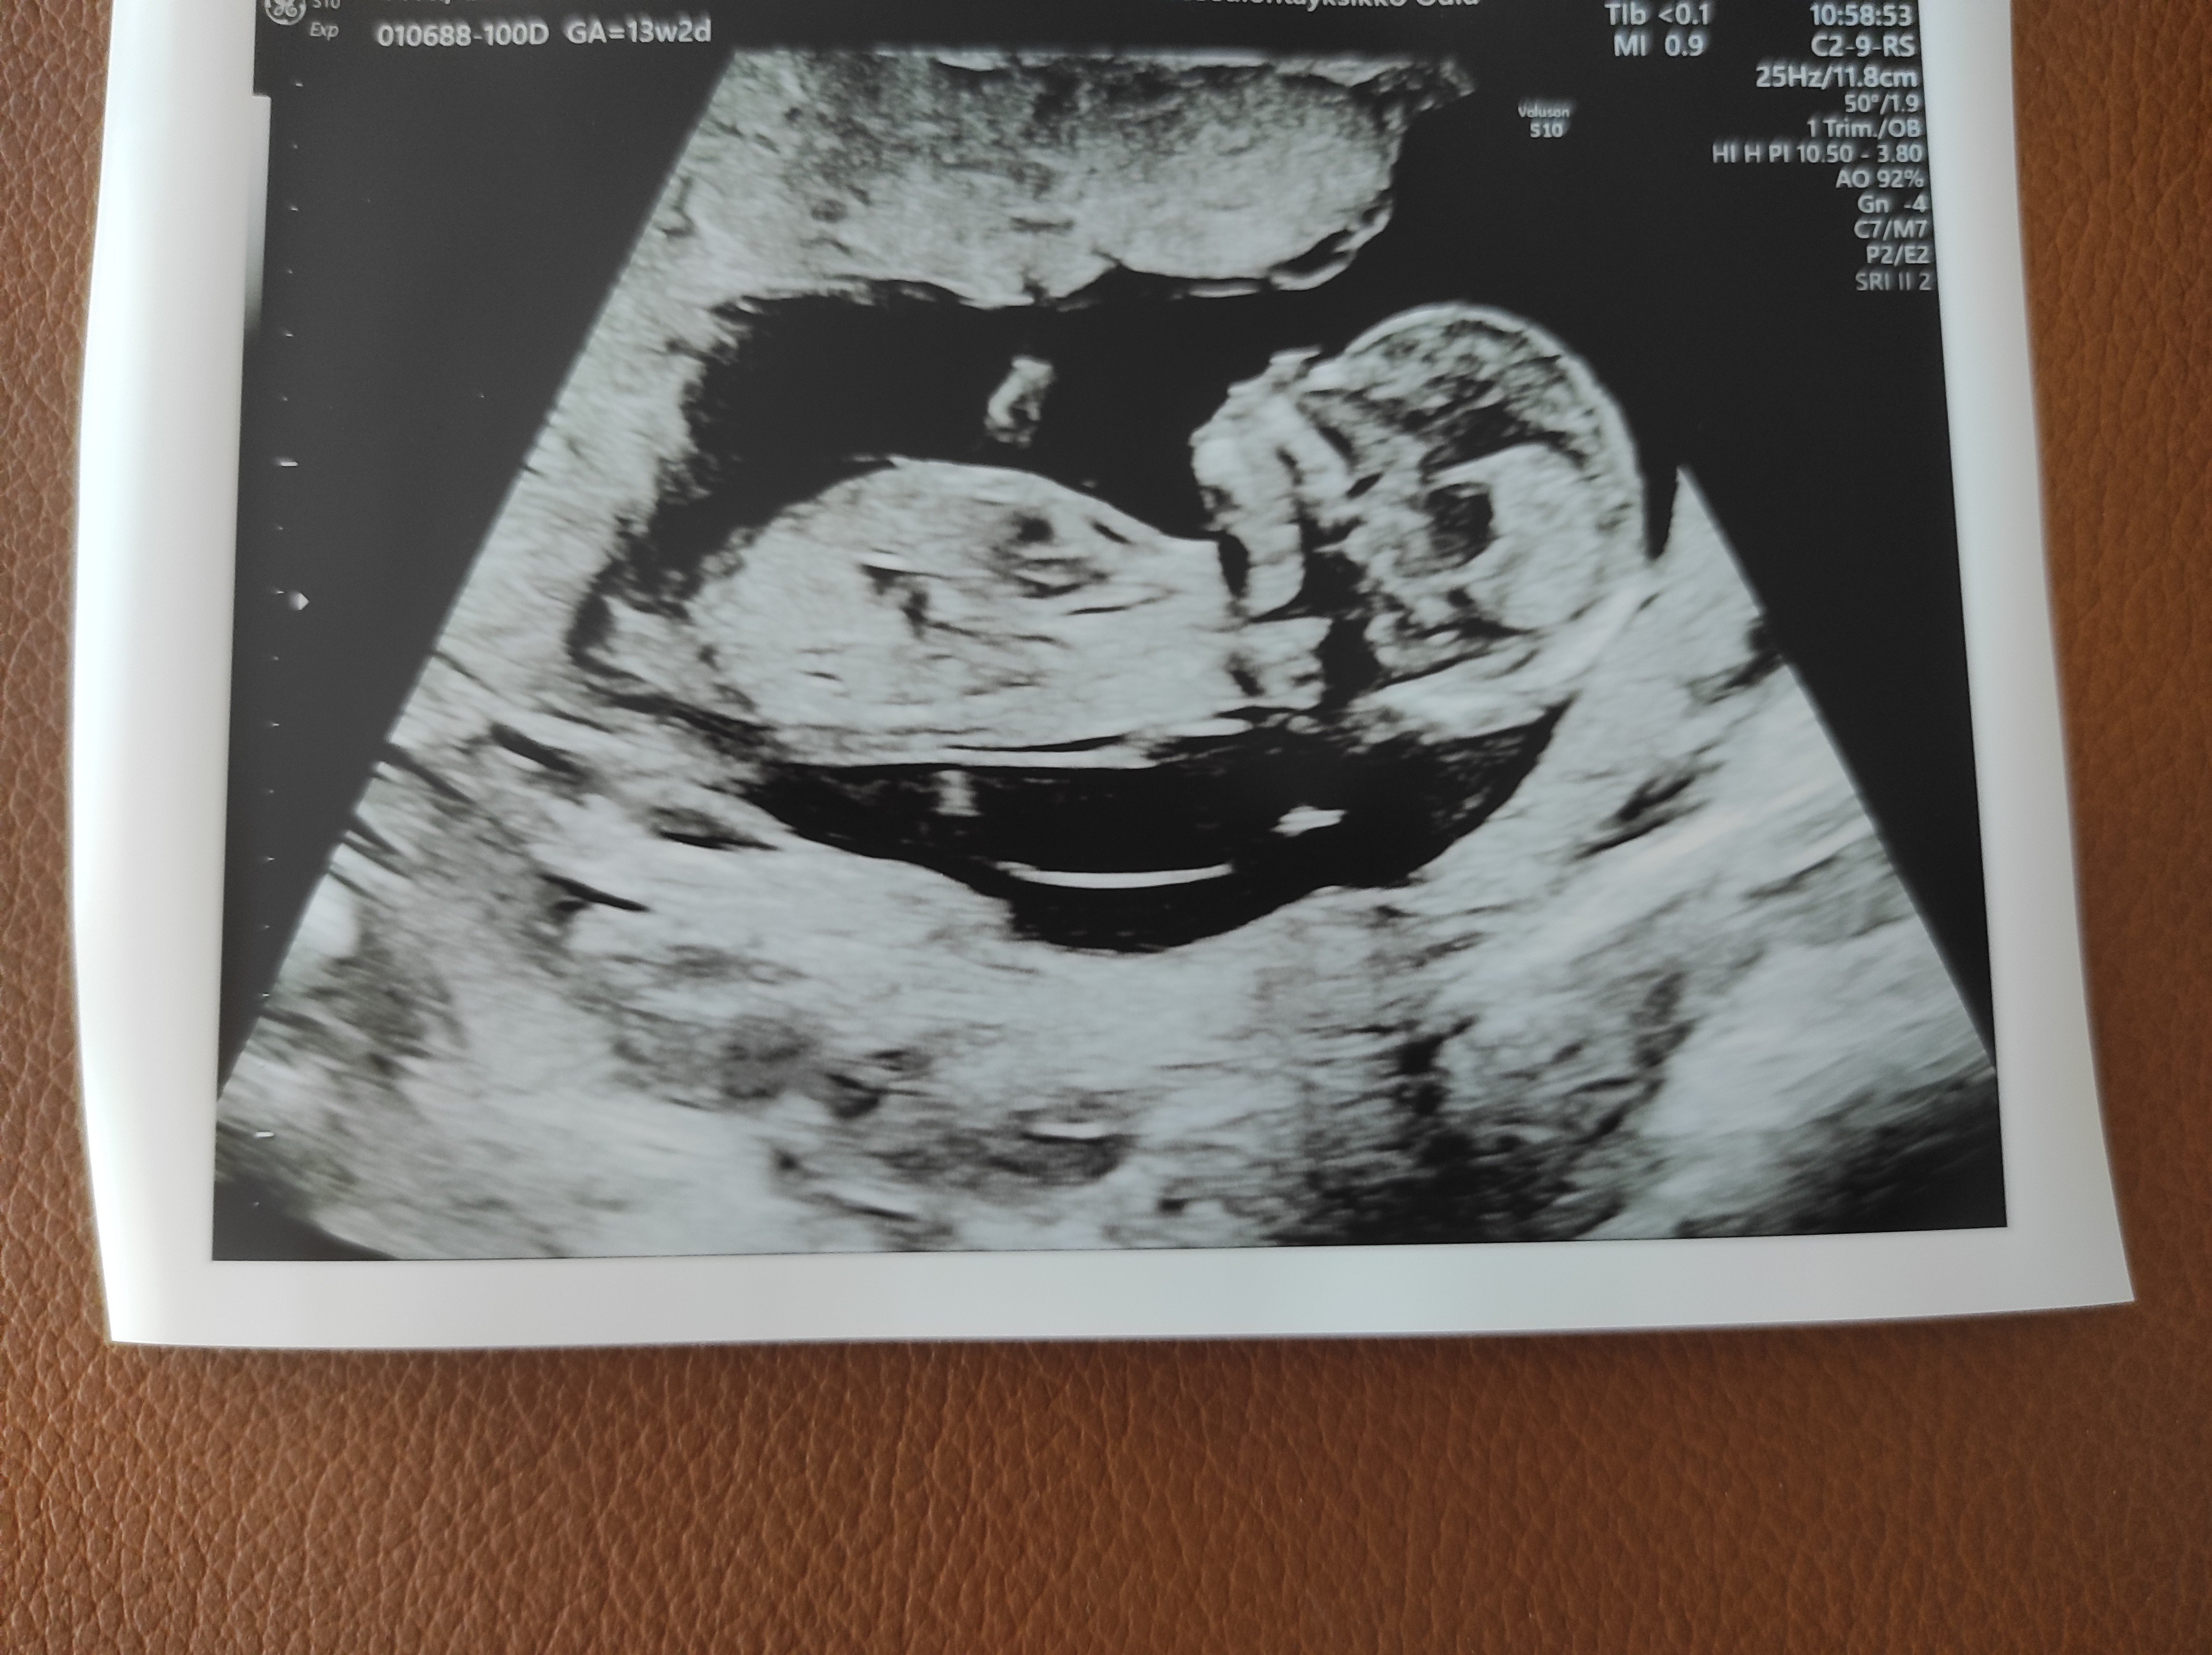

Heippa,

Osaako joku arvioida meidän kuvasta? Kätilö sanoi, että tuo ympyröity olisi napanupra, eikä siitä voi päätellä mitään. Facebookin nub-teoria ryhmässä sanottin, että se olisi nub?!

Rv 12+3.